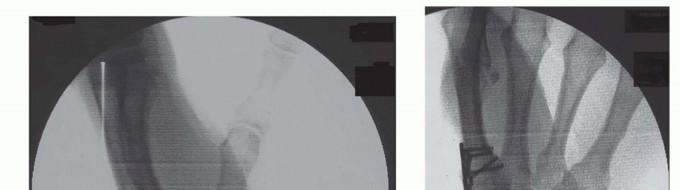

TECH FIG 3 • A. A six-hole plate is applied across the CMC joint. B. Two screws have been placed through the plate into the trapezium. C. Plate being applied onto the thumb CMC. D. Distal radius bone graft being packed into the CMC joint. Distal radius bone graft is then packed into the fusion site (TECH FIG 3D).At this time, final assessment of clinical alignment and fluoroscopic evaluation (position, bony contact, hardware placement/screw length) are performed (see FIG 2A,B).Irrigate the wound lightly with saline. Close the capsule with a nonabsorbable suture (3-0 Ethibond), repeat irrigation, and deflate the tourniquet to confirm hemostasis as the radial artery and venae comitantes are within the operative field. Close the skin with 4-0 nylon horizontal mattress sutures.If mild thumb MCP joint hyperextension is noted at this juncture, pin the MCP joint in 20 degrees of flexion with a single 0.045 Kirschner wire or consider a volar capsulodesis. In our experience, correction of the fixed flexion and adduction of the thumb metacarpal often improves MCP position with pinch so that operative intervention at the MCP joint is infrequent.Apply soft sterile dressings and a well-padded short-arm thumb spica splint.

FIG 2 • A,B. AP (A) and lateral (B) fluoroscopic images demonstrating application of plate and screws across thumb CMC joint.